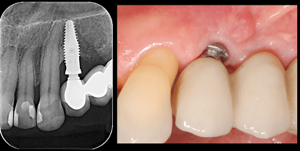

A peri-implantite é uma inflamação que afeta a gengiva e o osso ao redor de um implante dentário. Ela é parecida com a periodontite (que afeta os dentes naturais), porém, na peri-implantite, acontece especificamente em torno do implante

Essa inflamação pode causar sangramento, inchaço, dor e até a perda do implante, se não for tratada a tempo. O problema começa quando bactérias se acumulam na região e provocam uma reação inflamatória. Com o tempo, o osso que sustenta o implante pode começar a se deteriorar.